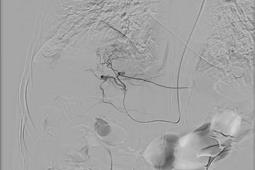

地区首例!创口0.5毫米,术后即可下床!四医院这项技术为肝癌介入治疗提供新选择